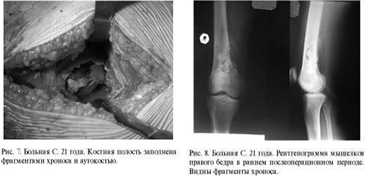

Больная Е. 36 лет. Диагноз: перелом медиального

мыщелка правой бедренной кости. На рентгенограмме определялся крупный дефект

медиального мыщелка бедра с внутрисуставным переломом оставшейся кости (рис. 2).

солитарная костная киста. Через 3 месяца наступила консолидация перелома (рис.

4). На контрольном осмотре через год у пациентки жалоб не было: ходит с полной

нагрузкой, разгибание и сгибание в коленном суставе - 100%. На рентгенограмме

прослеживается обычная костная ткань. Через 3 года: признаков рецидива опухоли

нет (рис. 5). Женщина работает, жалобы отсутствуют, от удаления опорной

пластины отказывается.